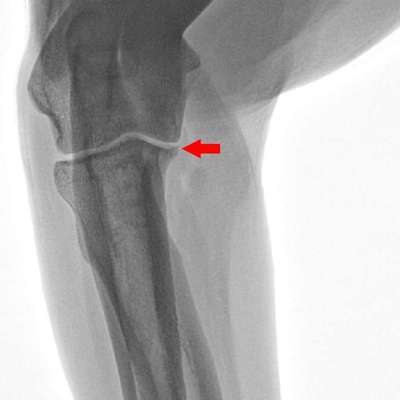

Ja wurde jetzt mal ein Röntgen bild gemacht aber schwer zu sagen

Ellenbogen TA findet es könnte da minimal Veränderung sein aber kann es nicht ganz genau sagen